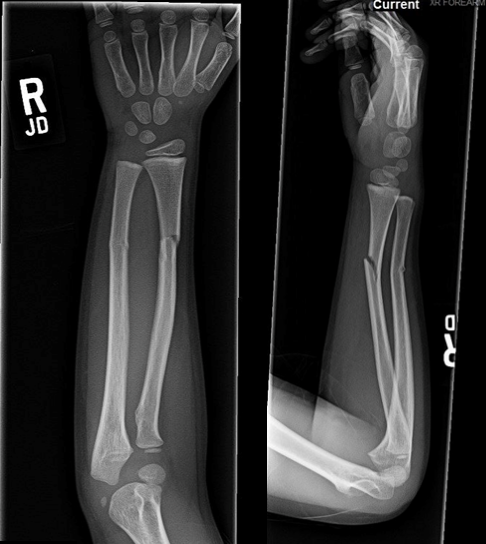

What is the diagnosis for the fracture of the radius and the causative mechanism?

A

Greenstick fracture

Angular/shear force (bending)

How well did you know this?

What is the diagnosis for the fracture of the ulna and the causative mechanism?

Torus fracture

Compressive/axial force